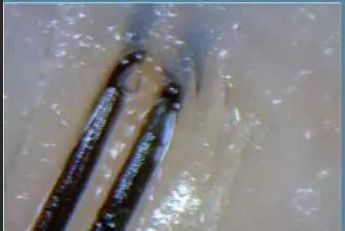

简单地说,毛囊检测是通过借助电子显微放大设备和专用的分析软件,将肉眼无法识别的头发细节检测出来。

在最终的检测报告上,从毛干到毛囊的健康程度都会完整的呈现出来。

用专业的毛囊检测设备,放大头皮画面,可以很直观的看到:头皮的颜色、毛囊萎缩坏死情况和毛囊分布密度,哪些头发即将脱落,哪些是新生长出来的头发等等。